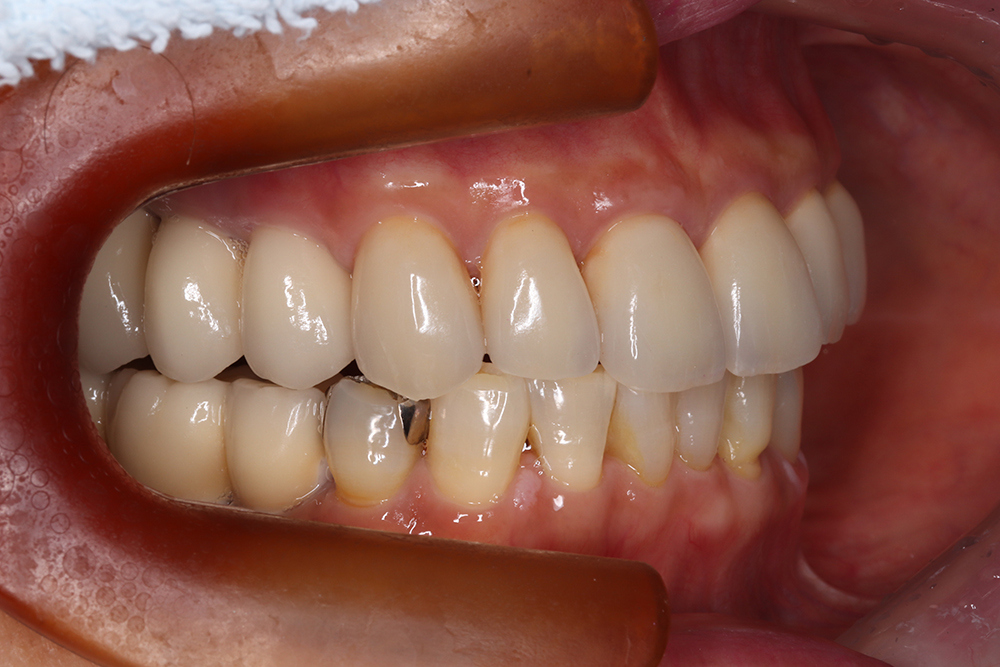

58歳 男性 歯科医療関係者紹介

- 主訴

- 右下を抜歯して噛めない

- 処置内容

- インプラント2本埋入

- 治療費用

- 約80万円(税込)

- 治療期間

-

8か月

仮歯完成まで5か月(この時点で噛めます)、+3か月で最終素材へ

- リスク

- 上部構造物、仮歯の破折、術後の腫れ(3日)、人工歯根脱落リスクがあります